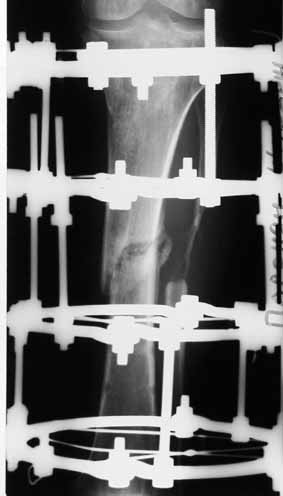

Рентгенологически определяется дистракционный регенерат удовлетворительной плотности и наличие в нем полости (now 1;2;3).

После последнего R- снимка 4 дня назад, аппарат переведен в режим фиксации.

Из 13 см исходного укорочения (опять-таки со слов больного) устранены 6. Бросающейся в глаза диспропорции между длиной голени и стопы уже нет. Хотелось бы удлинить еще на 4-5 см, тем более, что контрактур в смежных суставах голени практически нет. Вопрос: как поведет себя инфекция и будет ли адекватный дистракционный регенерат. Больной курит до двух пачек в день. Сроки лечения для него не принципиальны.

После первого сообщения, мы сбросили дистракцию 3 раза по 2 мм в течении 5-6 дней.

В настоящий момент ранки закрылись полностью. Получает ципринол по 500 ед х 2 раза в день. Планируем возобновить дистракцию, сделать R- контроль через 15 дней, а там видно будет.